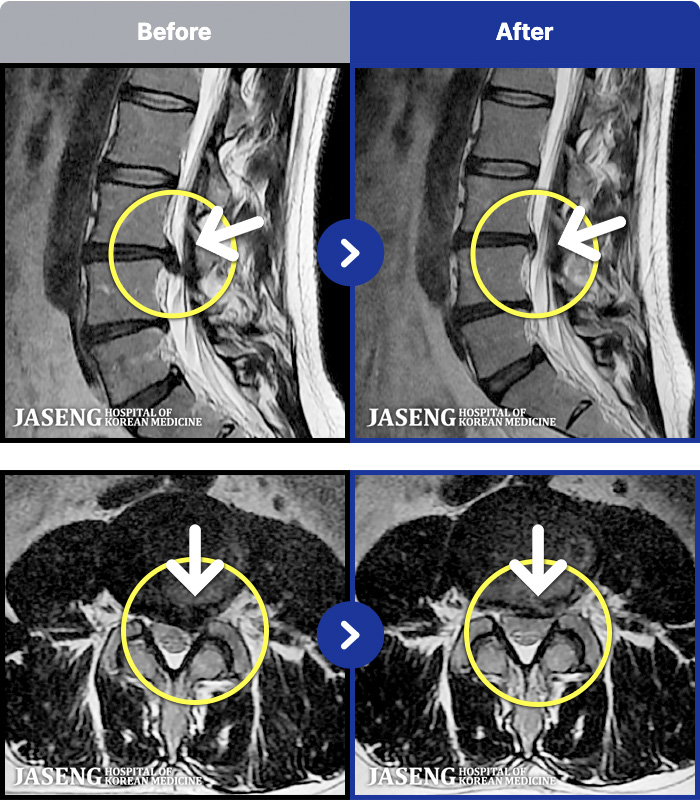

MRI ġ

1,240 MRI ũ ʸ Ȯϼ.